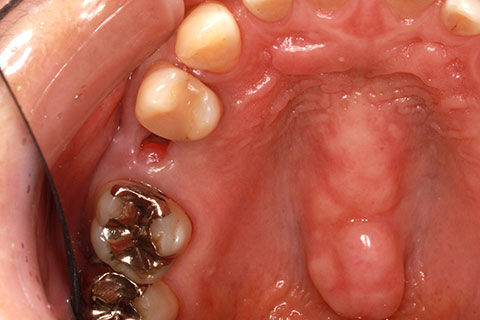

• ジルコニアブリッジの症例2

治療前

治療後

年齢・性別

40歳男性

治療期間

1ヶ月

抜歯

右上5番欠損

治療費

16.5万円

備考

歯質の削除量を最小限に抑えるブリッジ治療

治療内容

欠損部位の隣接歯を削合後、セメント合着

施術の副作用(リスク)

知覚過敏、歯髄炎、荷重負担